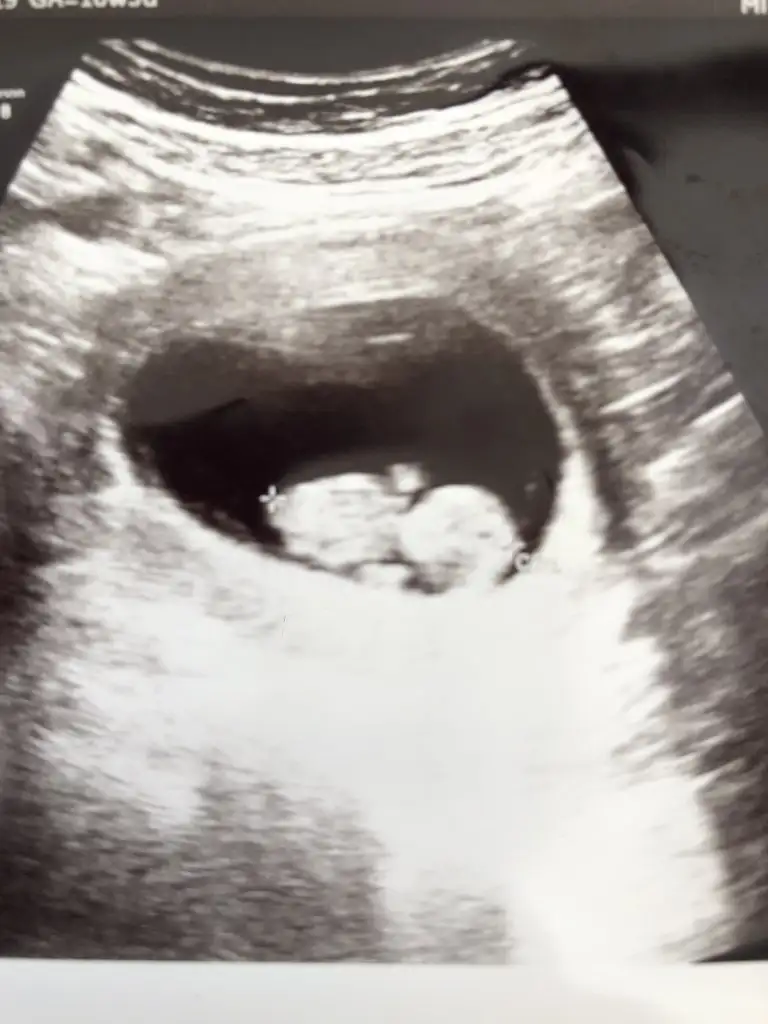

13+3 haftalık göstermedi bizimki tahmin yapabilir misiniz 🤣